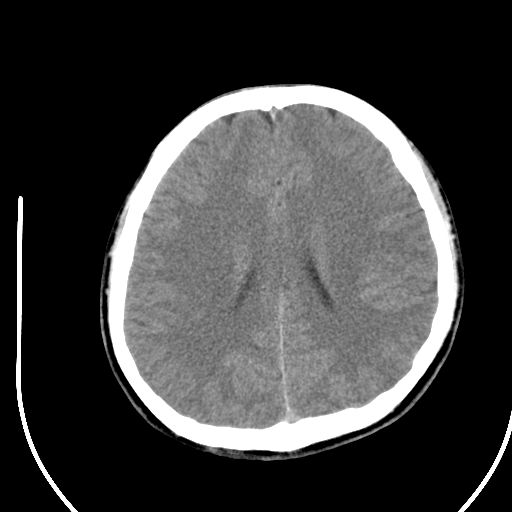

标题: CT28158:男,27Y。头痛数月,左顶叶血管瘤。 [打印本页]

标题: CT28158:男,27Y。头痛数月,左顶叶血管瘤。

海绵状血管瘤

考虑左顶叶海绵状血管瘤,建议mr检查。

左侧额叶海绵状血管瘤可能性大;建议行mri检查。

考虑血管畸形,因其周可见水肿,不除外感染性病灶。建议mri检查。